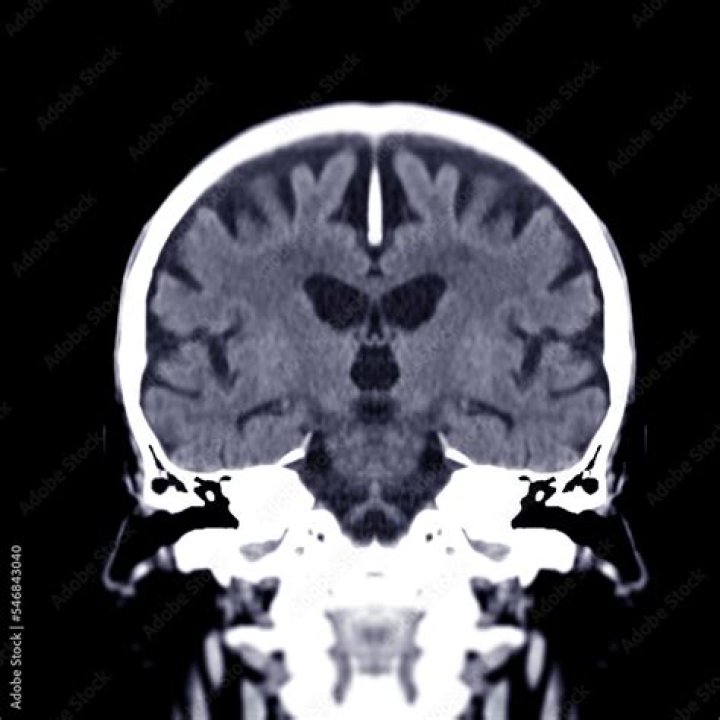

A coronal section is one that separates the brain into anterior and posterior halves. The coronal section shown in Figure 19a occurs approximately halfway between these two poles, and helps to show the placement of some of the major internal structures of the brain that will be referred to elsewhere.

A coronal plane (also known as the frontal plane) is any vertical plane that divides the body into ventral and dorsal (belly and back) sections. It is one of the three main planes of the body used to describe the location of body parts in relation to each other axis.

• This type of magnetic resonance imaging (MRI) study looks at the brain with 28 coronal (vertical – side to side) cuts that begin at the back of the brain and work forward.